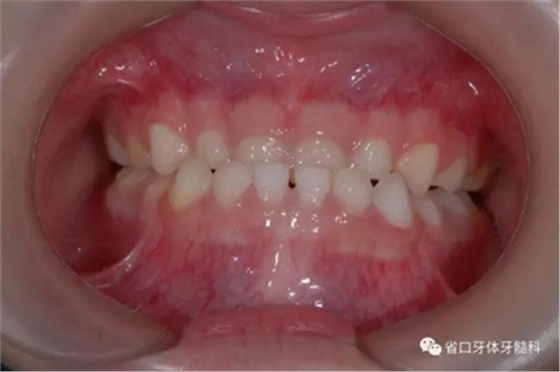

圖4 正面牙相(2015年1月)